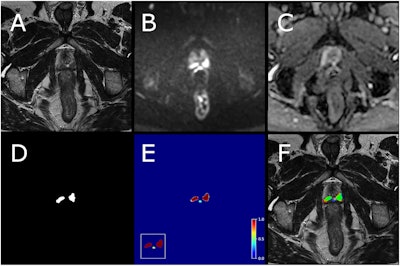

Example case from test set with biparametric MRI data, reference segmentation, and output from AI system. The primary MRI assessment resulted in a PI-RADS 5 lesion in the left dorsal part of the peripheral zone and a PI-RADS 4 lesion in the right dorsal part of the peripheral zone (PSA of 11.6 μg/L). Targeted biopsies from both areas showed ISUP-grade 3. All images are from the same slice location, showing a part of both lesions. A T2-weighted (T2W) image. B Diffusion-weighted image with a b-value of 1,500 s/mm2. (C) Apparent diffusion coefficient map. (D) Reference segmentation with white areas representing tumor. (E) Softmax output from AI system. Inset in the lower left corner shows the detection map (cropped around the prostate) with red voxels representing softmax values of 0.99 and yellow voxels representing softmax values of 0.59. (F) T2W image with reference (D) and detection map (inset in E) overlayed, green represents areas in which both the reference and the AI output are positive (true positive voxels for AI), red only positive in reference (false-negative voxels for AI) and blue only segmented by AI (false-positive voxels for AI). Fredrik Langkilde et al; European Radiology.